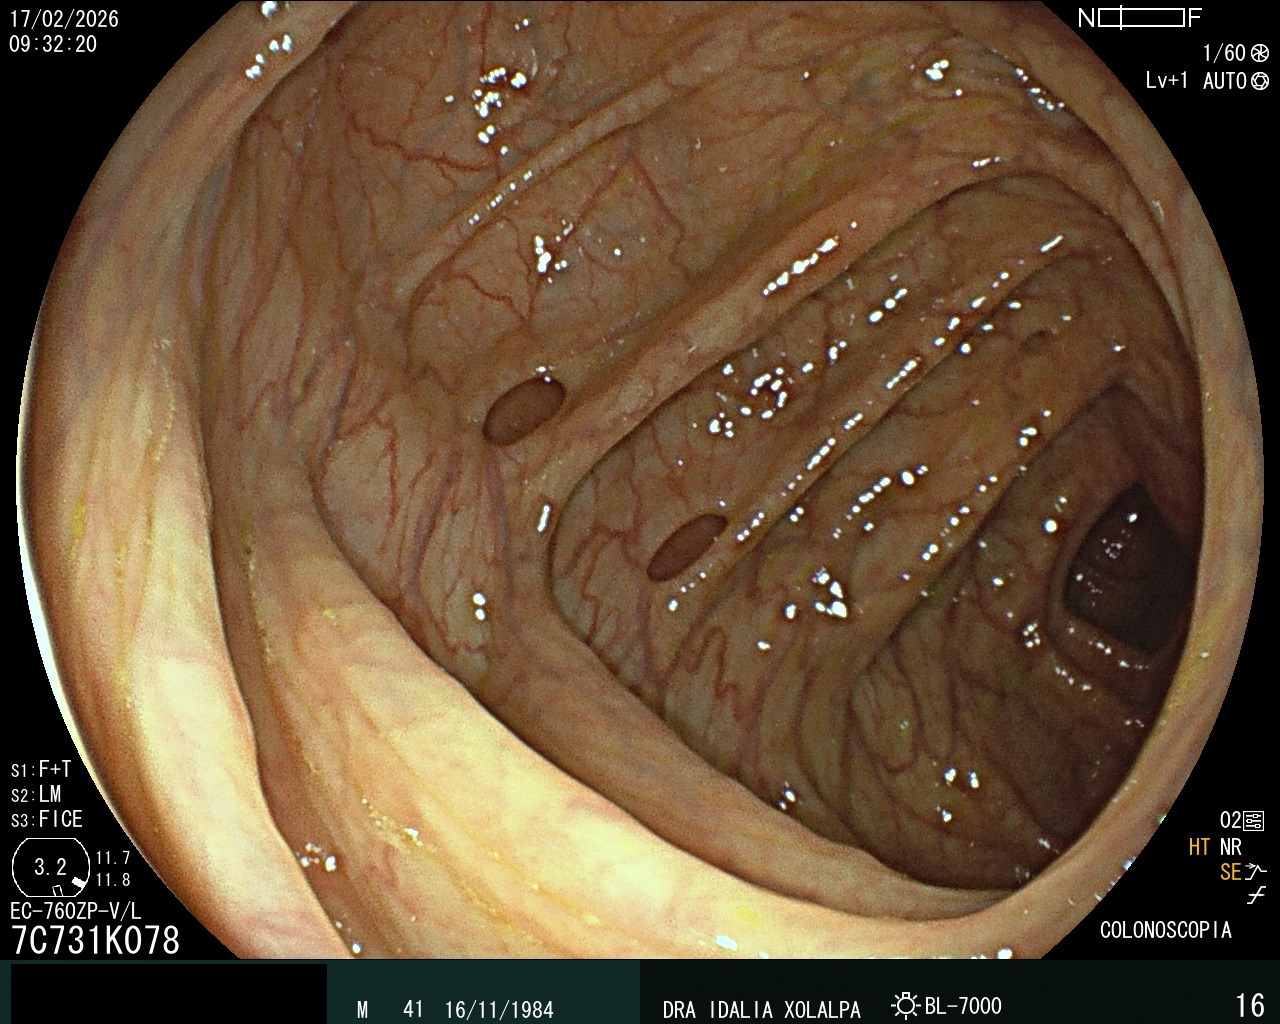

Divertículos

Identificación de divertículos en colon